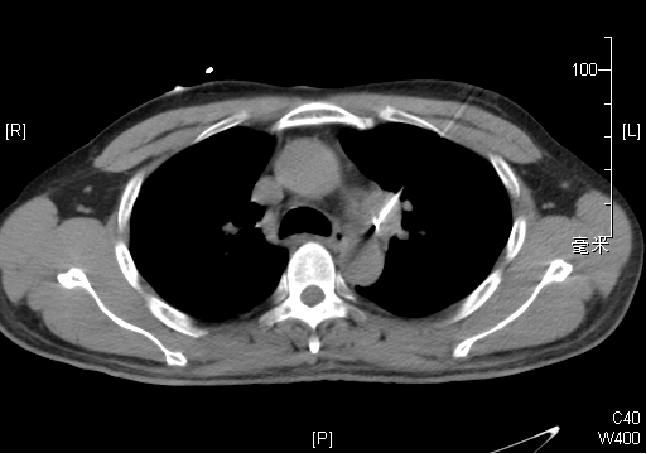

2016.12:双肺门及纵隔未见明显肿大淋巴结

2017.5:主-肺动脉窗新增一肿大淋巴结,大小约19mm×23mm

2017年5月第四次介入治疗:纵膈淋巴结射频消融

Cool-tip 200W/10min